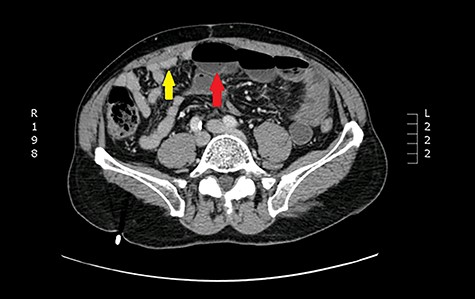

One year later, he was readmitted with small bowel obstruction investigated with an abdominal computed tomography (CT) scan that showed no radiological finding of stenotic Crohn disease or other obstructive etiology (Figs 2 and 3).

Coronal view: arrows pointing to dilated and collapsed small bowel.